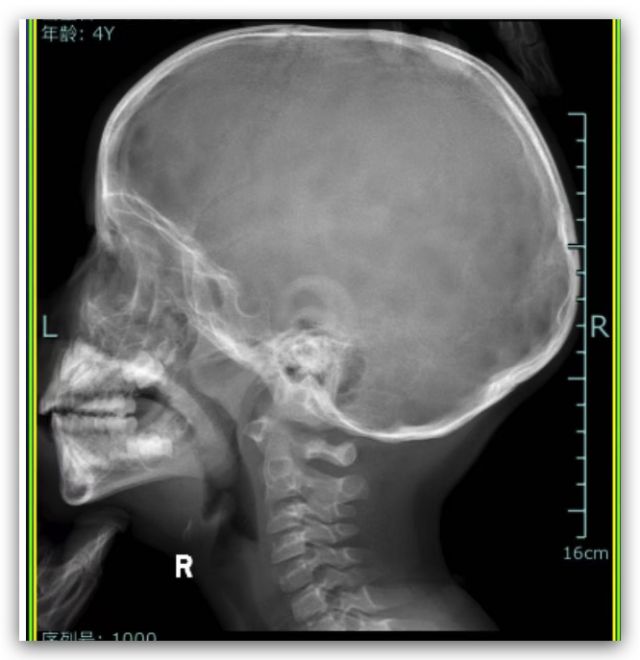

症状如图,拍片钱用鼻喷激素月余和口服西替利嗪月余,拍片时稍微有点小感冒,医生说手术切除,老婆担心全麻,求问下nga,这种情况要切吗?